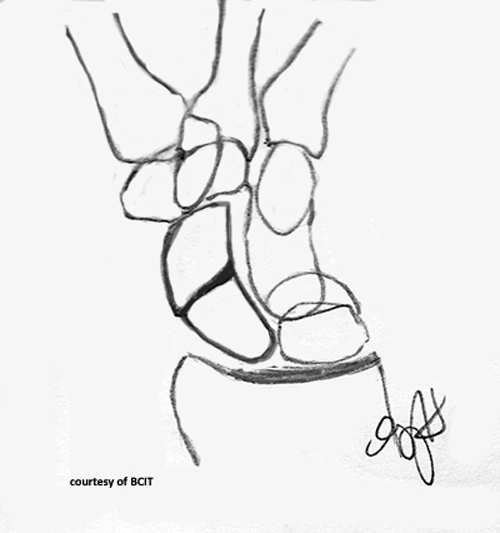

What does a 'spilled teacup' appearance indicate on lateral wrist imaging?

Lunate dislocation.

What causes lunate dislocation and what are its features?

FOOSH injury; volar displacement, loss of articulation with capitate and radius.

The alignment of the third metacarpal, capitate, lunate, and radius on a lateral view (the “teacup” effect).